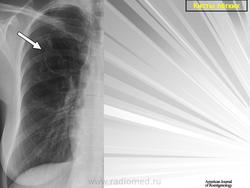

Воздушные кисты

Легочные кисты.